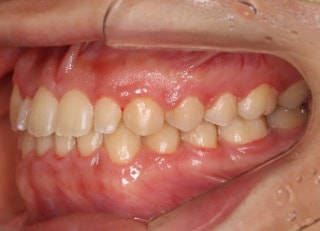

治療前